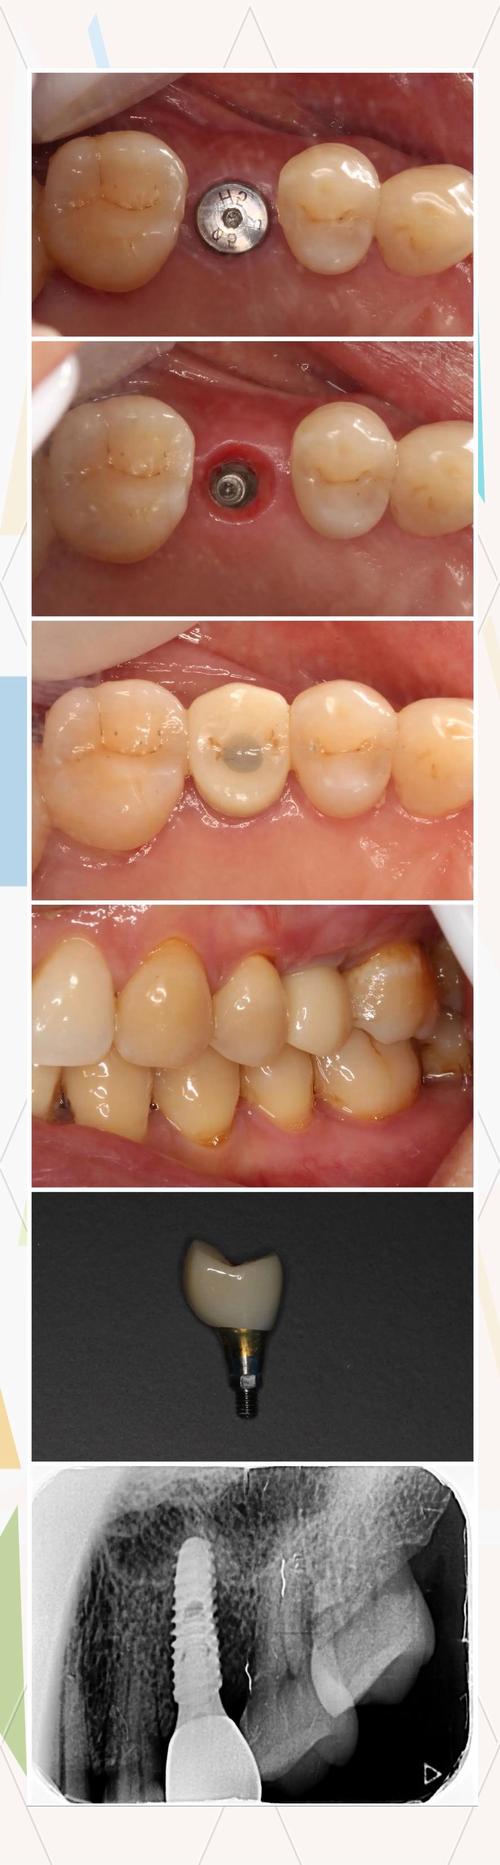

拔牙半年后,当牙槽骨条件符合种植要求时,便可正式启动种牙流程,整个过程可分为术前检查、种植体植入、基台安装、牙冠修复四个阶段,每个阶段均需严格把控细节,以确保种植效果。

种植体植入:精准操作,确保初期稳定

种植体植入是手术的核心步骤,通常在局部麻醉下进行,过程约30-60分钟:

- 消毒与麻醉:口腔内常规消毒,局部浸润麻醉或阻滞麻醉,确保手术无痛。

- 切开与翻瓣:在牙龈上做切口,翻开黏骨膜瓣,暴露牙槽骨。

- 备洞与植入:根据种植体直径和长度,使用逐级备洞钻头在牙槽骨中制备种植窝,过程中不断用生理盐水降温,避免骨灼伤,随后将纯钛或钛合金种植体(生物相容性极佳,能与骨组织结合)旋入种植窝,确保初期稳定性(种植体无松动,扭力达到35-50N·cm以上)。

- 缝合与愈合:缝合牙龈切口,拍摄术后X线片确认种植体位置,术后无需住院,遵医嘱服用抗生素、止痛药,1周后拆线。

骨结合期:等待“种植体-骨”界面融合

种植体植入后,需经历3-6个月的“骨结合期”:种植体表面的钛与周围的骨细胞直接接触,形成“骨整合”,种植体逐渐被骨组织包裹,成为“人工牙根”,此阶段需避免种植体受力,不要用患侧咀嚼,戒烟限酒,控制血糖(糖尿病患者),定期复查(术后1个月、3个月),通过X线观察骨结合情况。

基台安装与牙冠修复:完成“仿生牙”搭建

骨结合完成后,进入二期修复:

- 基台安装:切开牙龈,暴露种植体顶部,将基台(连接种植体与牙冠的部件)旋入种植体,调整牙龈袖口形态,为牙冠提供支撑。

- 牙冠制作与佩戴:通过数字化印模或传统取模,将模型送加工厂制作牙冠(全瓷冠、烤瓷冠或金属冠),1-2周后试戴,调整咬合和颜色,确保舒适美观后粘固完成。